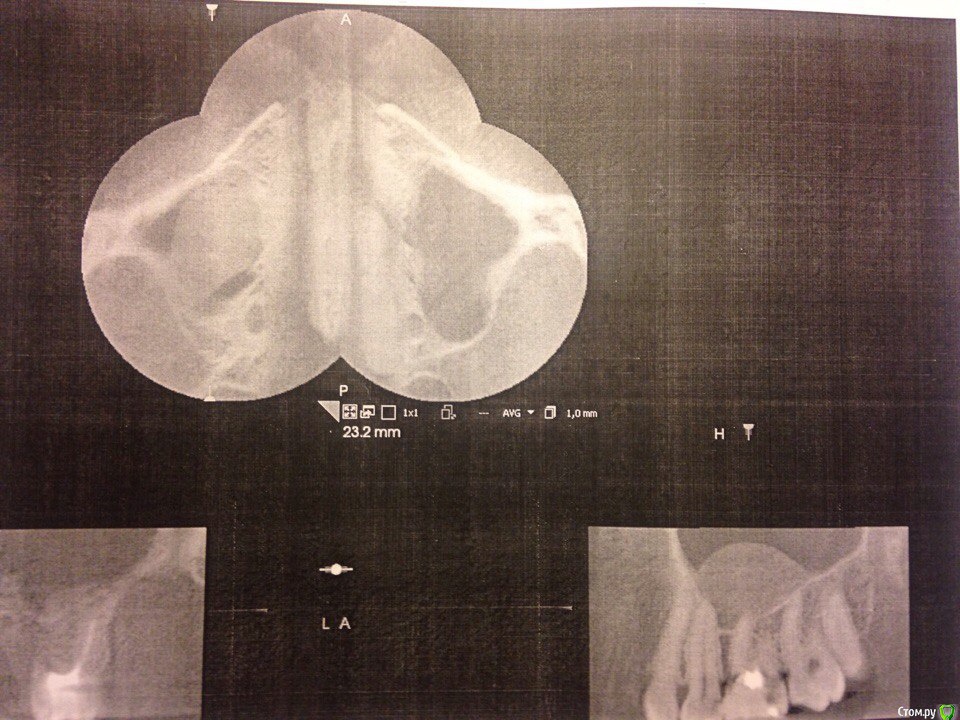

Через 2 месяца решил сделать МРТ носовых пазух и обнаружил, что киста с момента когда я делал МРТ головного мозга выросла. 2,1 на 1,6 см и она связана с корнем 6 зуба верхней челюсти с правой стороны.post-51349-0-57816600-1492620580_thumb.jpg post-51349-0-75262500-1492620585_thumb.jpg post-51349-0-12200600-1492620627_thumb.jpg

В день когда я записался к хирургу, который мне устанавливал имплант, протез выпал совсем. Голова стала болеть немного меньше, но все равно болела. По настоянию врача сделал прицельный рентген где установлен сам имплант и КТ всей челюсти для определения кисты.post-51349-0-78543900-1492620486_thumb.jpg post-51349-0-84336600-1492620557_thumb.jpg Я все сделал и врач установил, что имплант стоит прочно и следует просто заново поставить протез, но лучше по отдельности(не общий для 2 зубов). На КТ кисту он тоже нашёл и направил к челюстному-лицевому хирургу. Поставил мне временный штифт(не знаю как назвать), и на следующий день голова опять начала болеть как прежде.